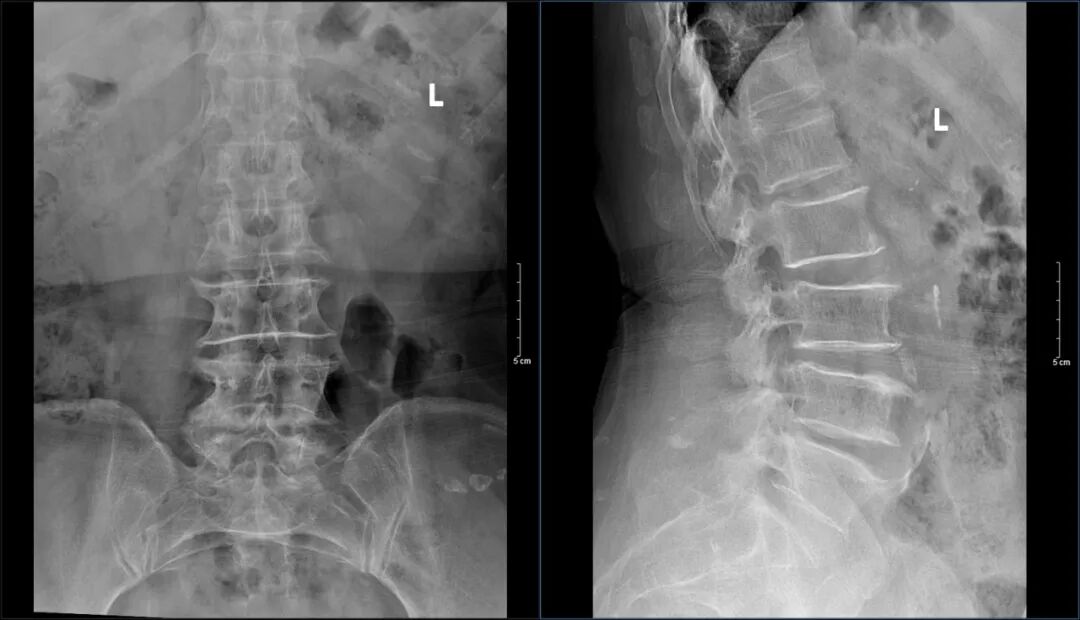

据了解,患者今年69岁,被腰椎间盘突出的症状困扰已有10余年的时间。期间通过口服药、理疗治疗,症状反反复复,极大困扰了患者的正常生活。近几年腰痛症状加重伴双下肢酸胀、麻木,右下肢症状最为明显,行走跛行,步行约100米需休息后可继续行走。为进一步治疗,来到济南南郊医院骨科就诊。济南南郊医院骨科脊柱小组医师接诊后详询病史、查体阅片,患者腰椎生理曲度变直,腰椎向左侧轻度侧弯,L3/4,L4/5,L5/S1棘突间压痛明显,建议患者住院治疗。

现患者腰痛伴双下肢酸胀麻木,活动后加重,不能久走、久站,保守治疗效果差,明显影响日常生活及劳动能力,相关辅助检查结果已证实术前诊断,具备手术指征,已排除手术禁忌证。根据术前查体及医学影像检查,脊柱外科手术团队进行术前案例研讨,制定了“经后路L3/4、L4/5椎管减压+椎间盘切除+椎间植骨融合钉棒内固定术”的方案,并对可能发生的紧急情况制定了相应的预案。